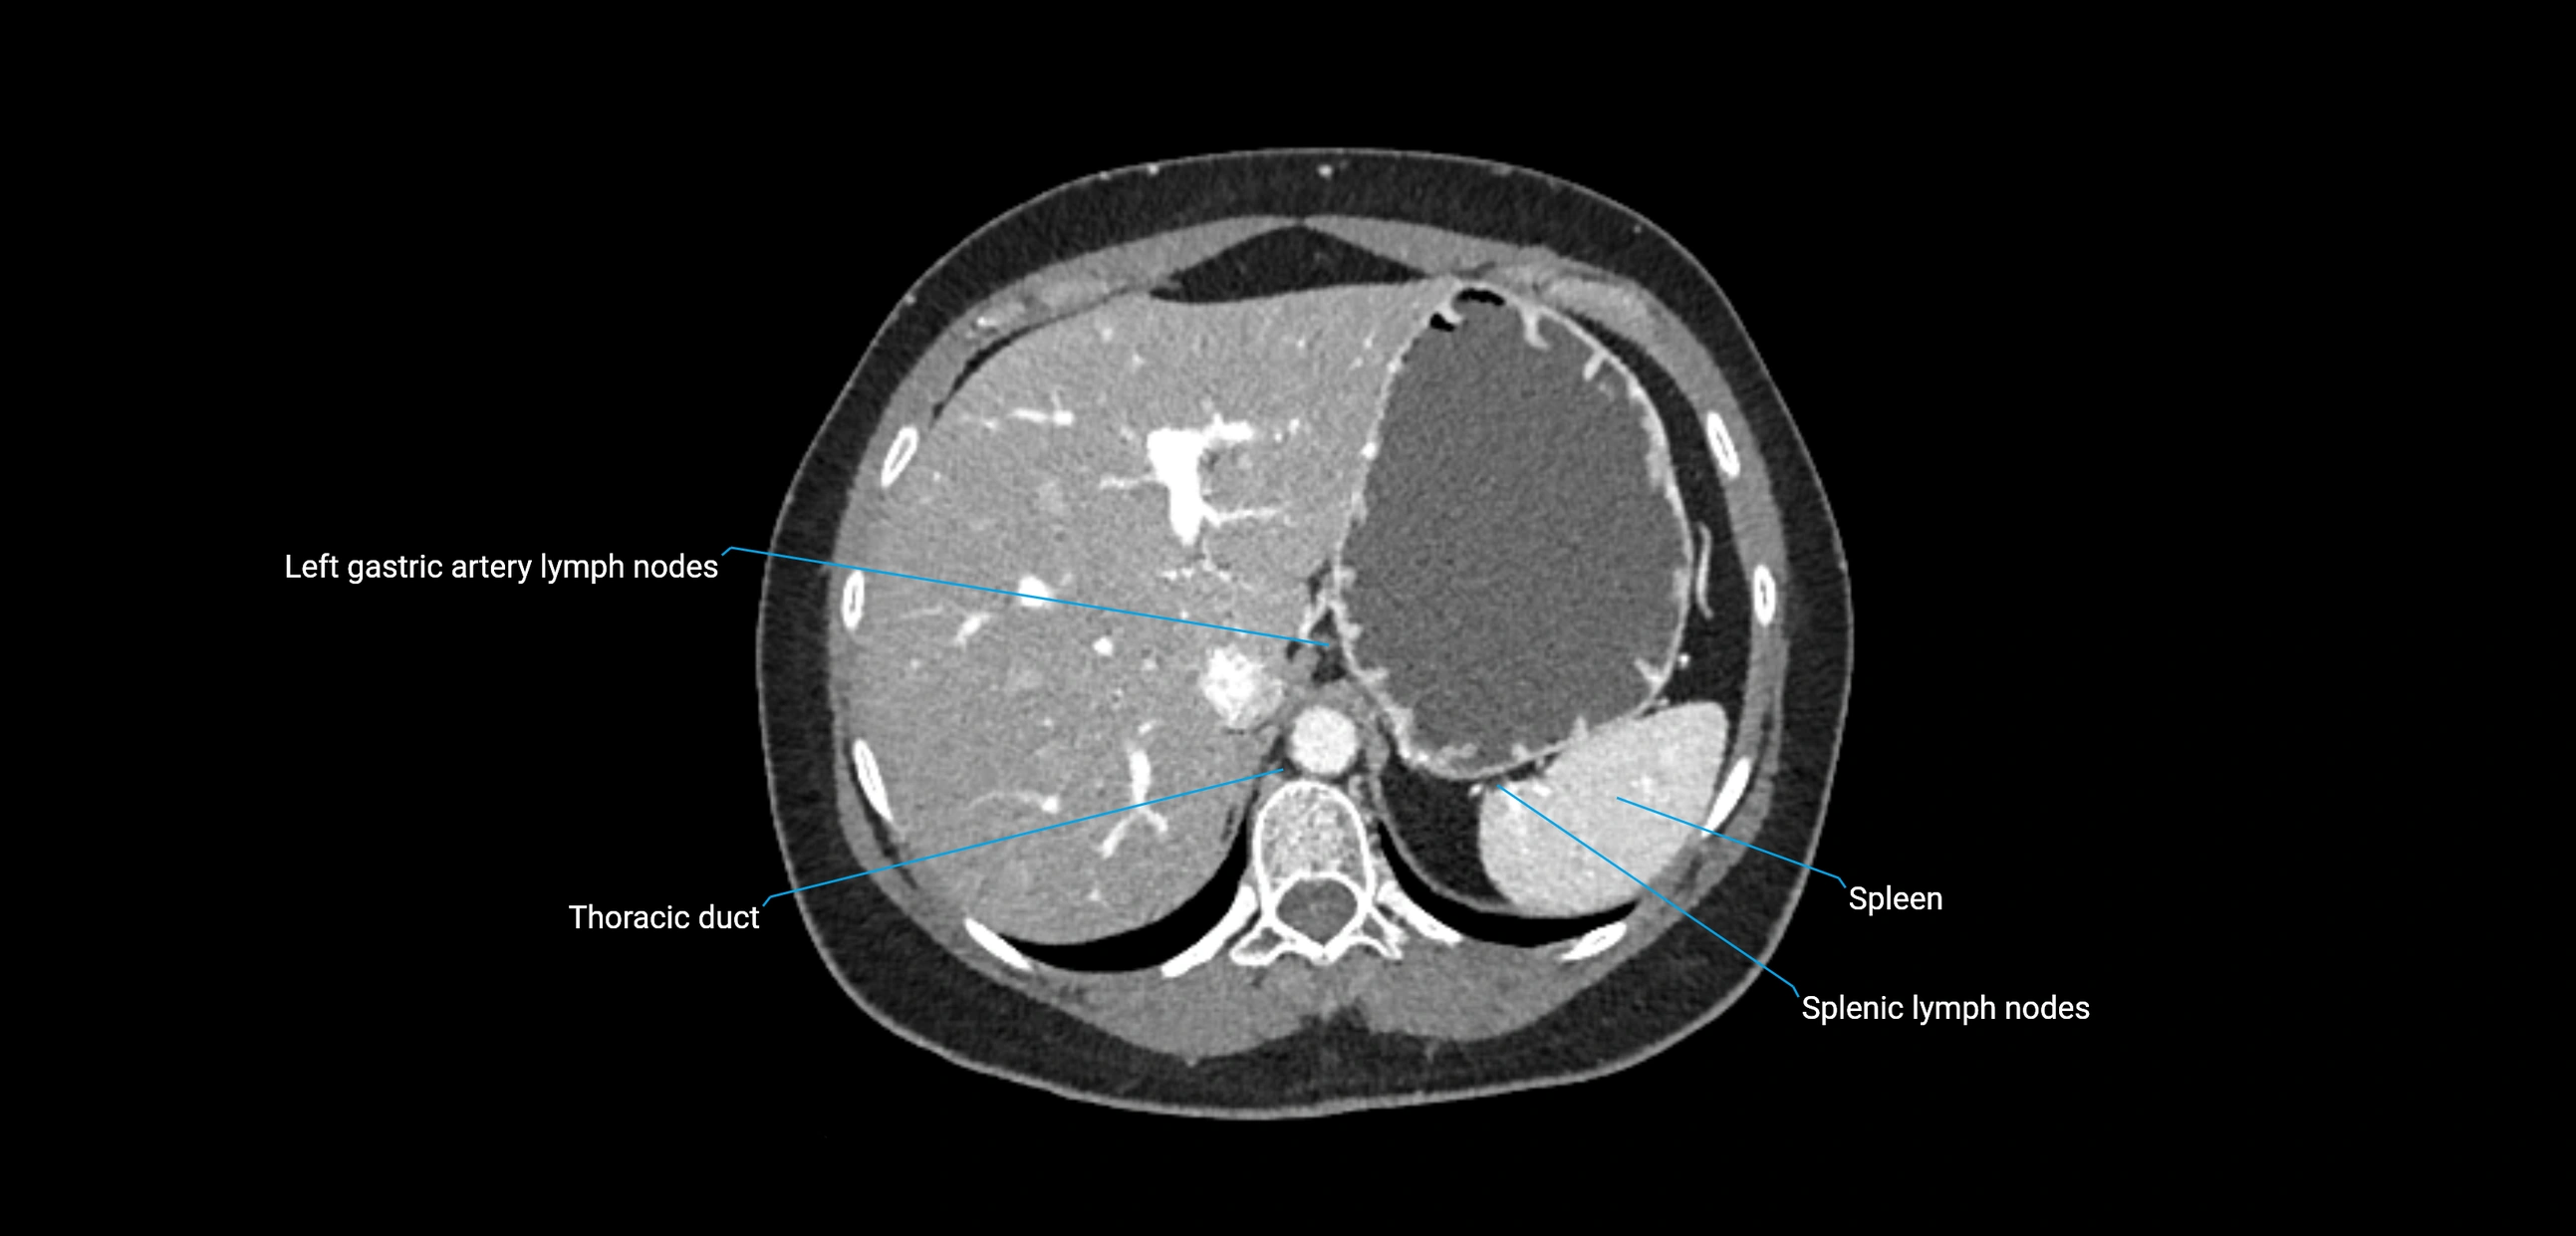

CT Post-Contrast:

• Normal nodes enhance homogeneously

• Malignant nodes may show heterogeneous enhancement, central necrosis, or conglomerate formation

• Size >1 cm short axis is suspicious, though morphology and distribution are equally important

CT Venography (CTV):

• Demonstrates nodal encasement or compression of adjacent vessels (aorta, IVC, renal veins)

• Useful in staging testicular and ovarian malignancies

• Provides 3D reconstructions for retroperitoneal lymph node dissection planning